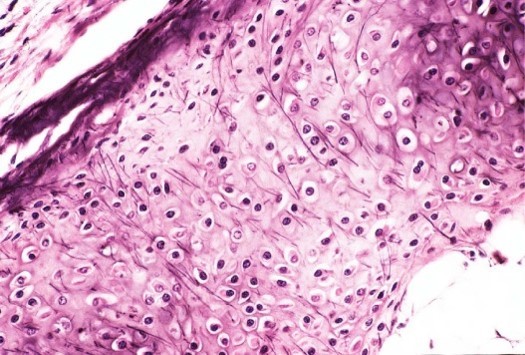

Hyaline cartilage